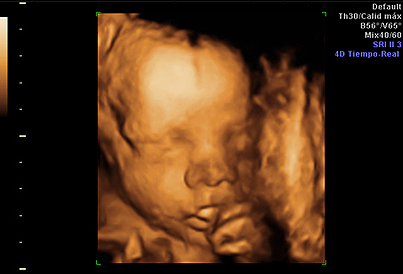

La exploración mediante ecografía de cuatro dimensiones permite la reconstrucción en movimiento real de estructuras fetales, tales como la cara o los miembros fetales. En Hospital Universitario Quirónsalud Madrid se ofrece la posibilidad de realizar un estudio ecográfico 4D.

Dicho estudio no forma parte de las pruebas solicitadas durante el seguimiento de una gestación normal, y la cita debe solicitarse telefónicamente o de forma presencial en las consultas de Ginecología del hospital. Aconsejamos que la cita se solicite entre la semana 26 y 30 de la gestación, para optimizar la visualización de las estructuras fetales. Para la correcta visualización de la cara, es necesario que el feto se encuentre en una posición determinada sin tener estructuras por delante (como, por ejemplo, una mano) que dificulte la transmisión de la imagen. La exploración ecográfica será grabada en DVD que será entregada al finalizar.

Aparte de la obtención de imágenes tridimensionales del feto, durante esta ecografía se suele realizar un estudio anatómico fetal completo similar al realizado durante la ecografía morfológica del segundo trimestre.

Ecografía 4D en el tercer trimestre.